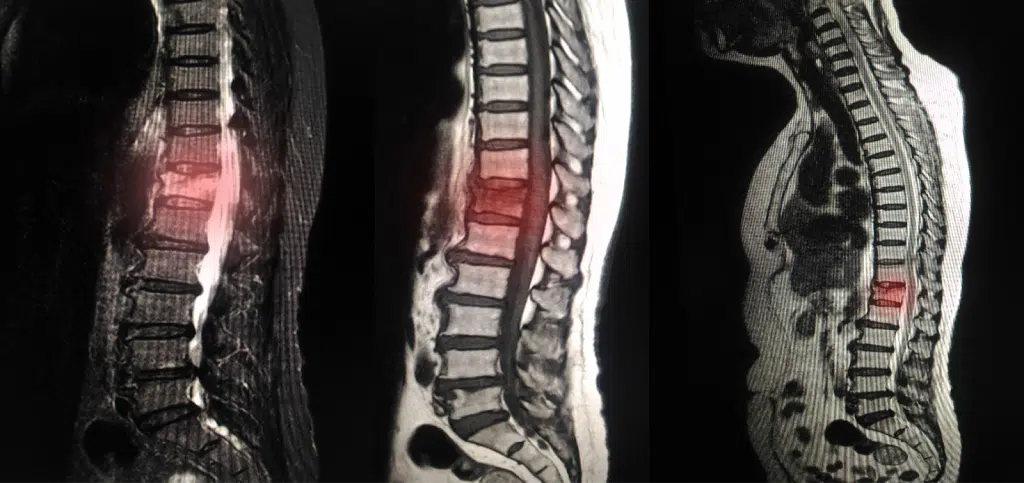

ام آر آی کمر یکی از دقیق ترین روش های تشخیص مشکلات ستون فقرات و دیسک های بین مهره ای است و به همین دلیل قیمت آن نسبت به سایر روش های تصویربرداری بالاتر است. قیمت ام آر آی کمر ممکن است در مراکز دولتی کمتر و در مراکز خصوصی به دلیل تجهیزات پیشرفته و خدمات جانبی بالاتر باشد.

قدرت و تکنولوژی دستگاه MRI تاثیر مستقیم روی قیمت تصویربرداری کمر دارد. دستگاه هایی با قدرت میدان مغناطیسی بالاتر، مثل دستگاه ۳ تسلا، تصاویر با وضوح و جزئیات بیشتری ارائه می دهند. استفاده از این دستگاه ها به دلیل تکنولوژی پیشرفته تر، هزینه ام آر آی دیسک کمر بالاتری دارد اما کیفیت تصویر برداری آن ها به تشخیص دقیق تر بیماری ها کمک میکند.